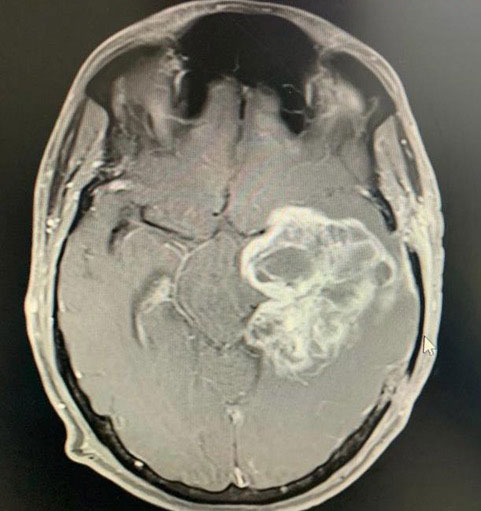

Surgical Highlights